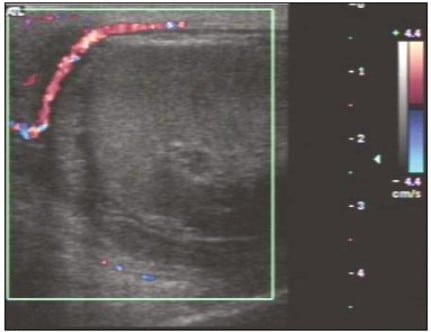

Tumores testiculares

Tumores testiculares, como neoplasias primárias dos testículos, também devem entrar nos diagnósticos diferenciais. De forma geral, podemos encontrar na ultrassonografia massa hipoecogênicas ou heterogêneas, vascularização aumentada nas bordas e ainda calcificações ou cistos associados.